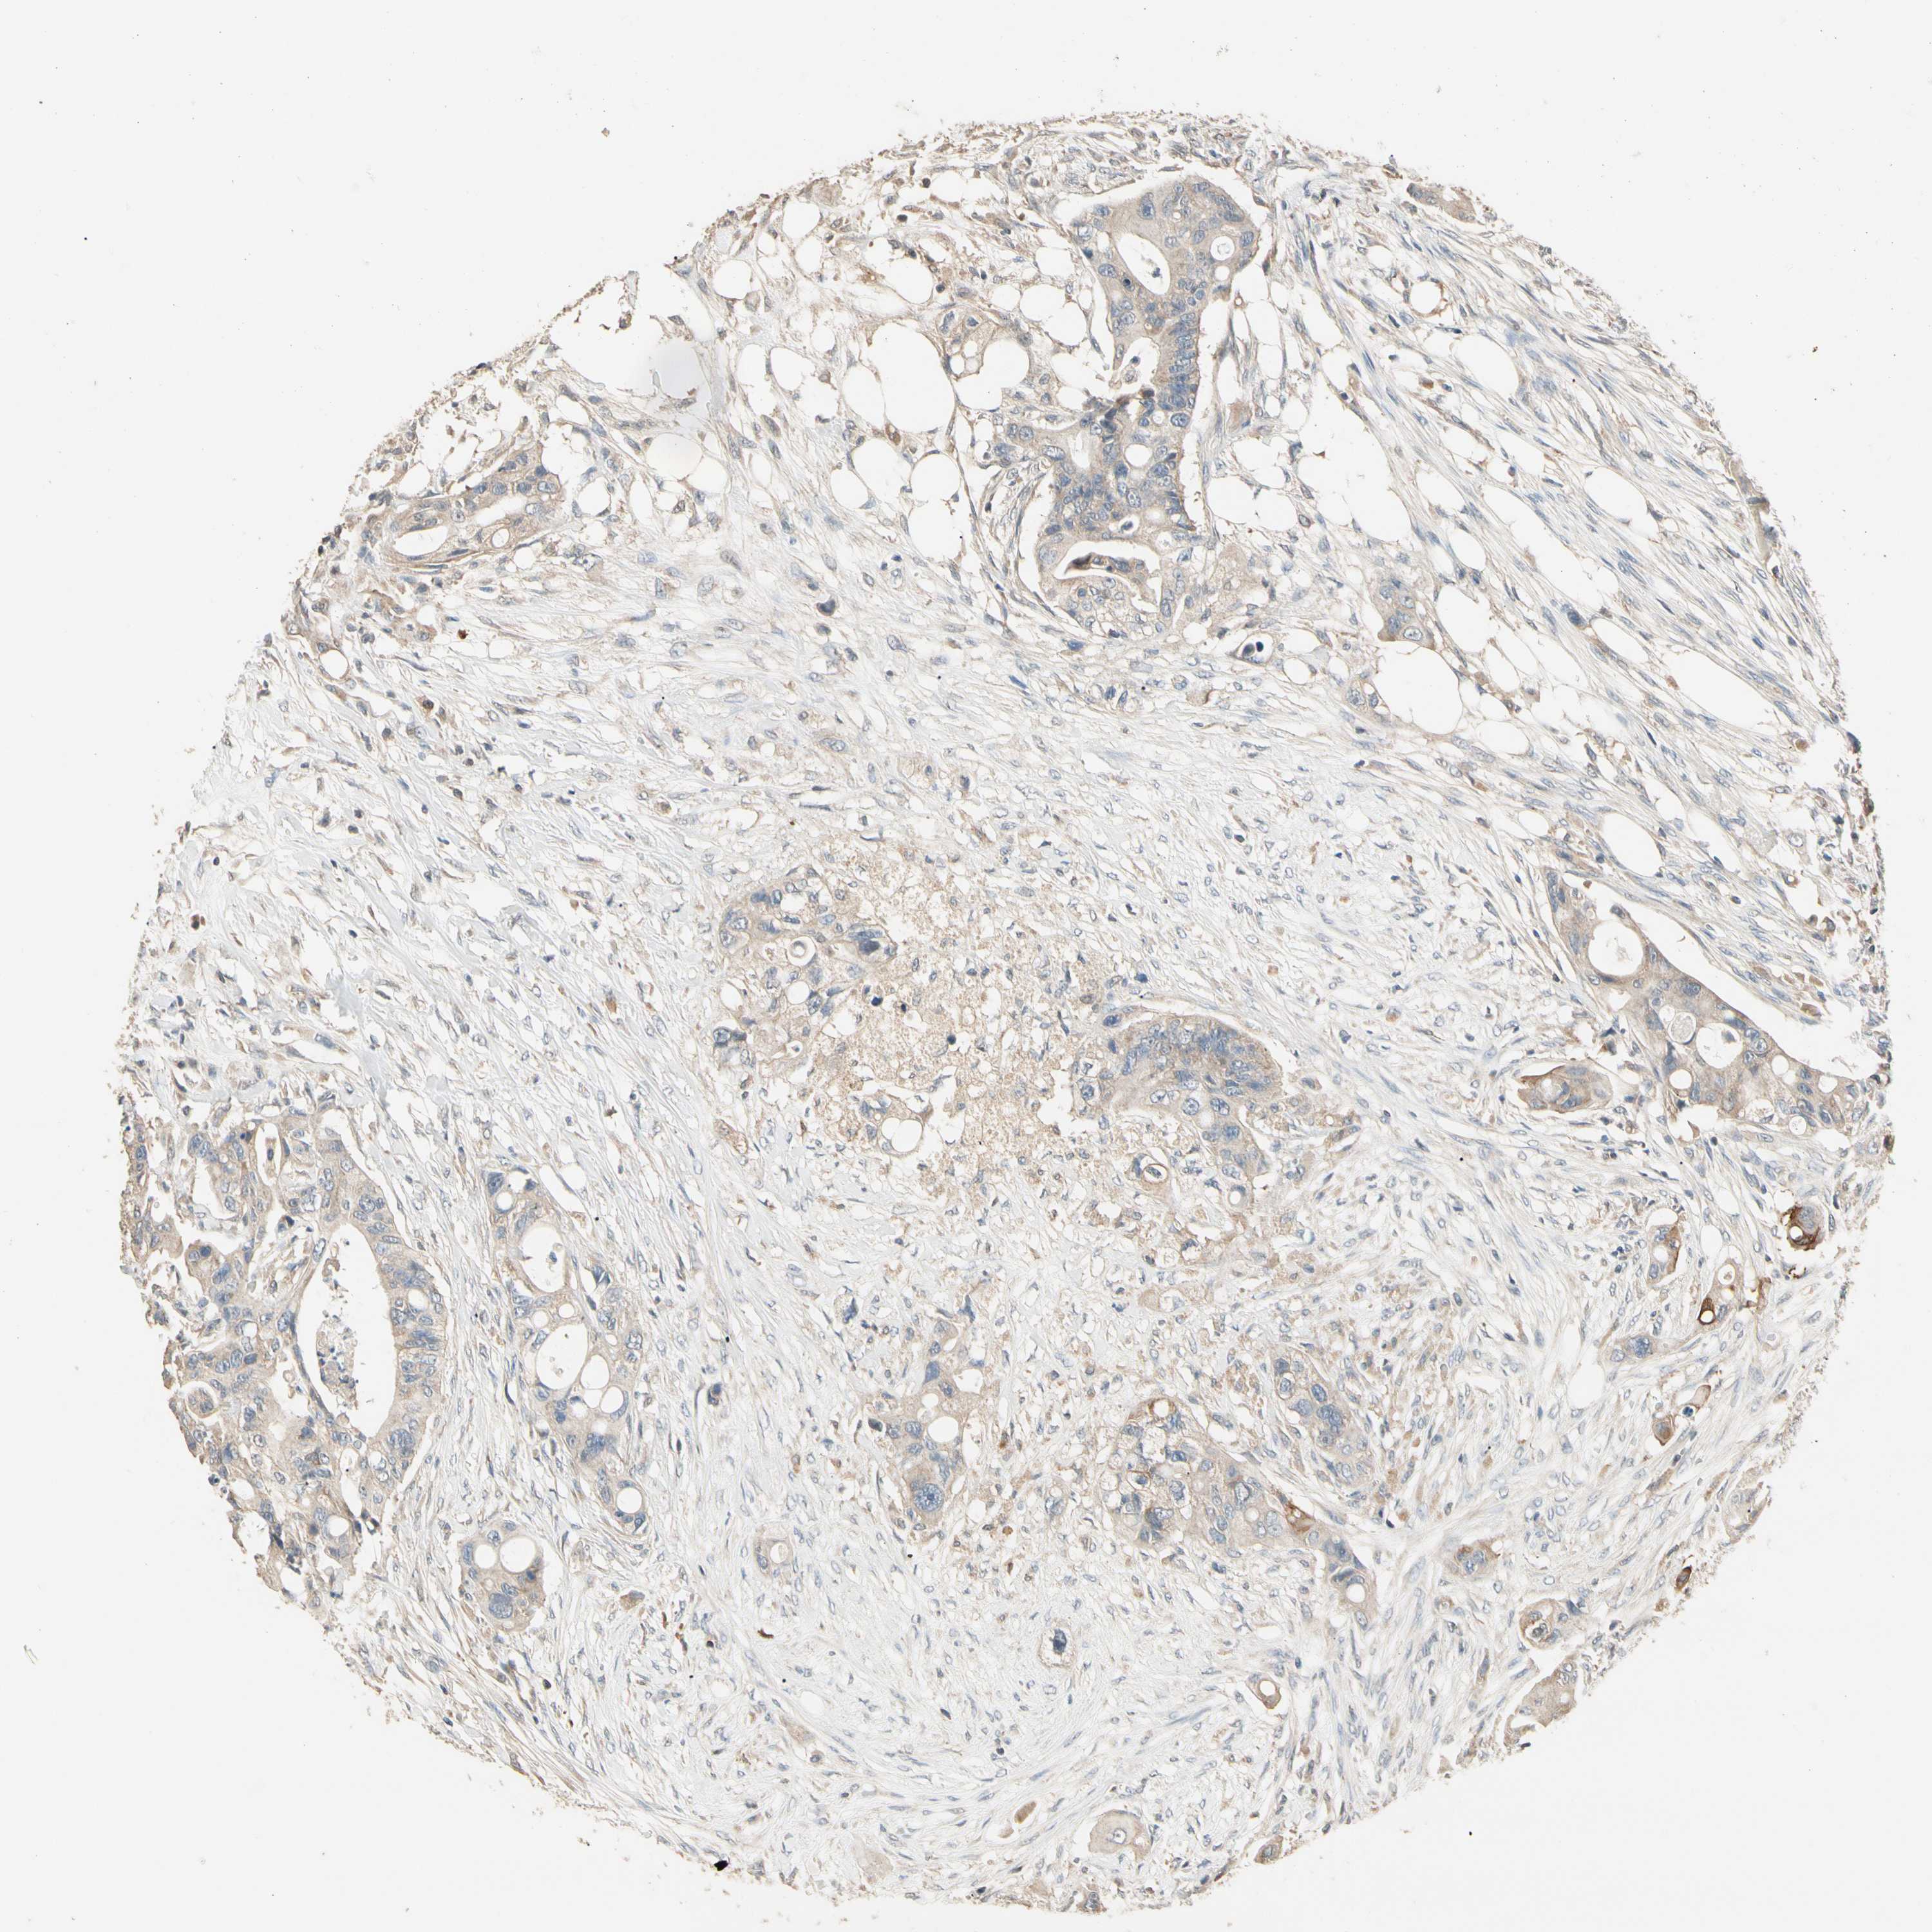

Colorectal cancer

Rectum adenocarcinoma